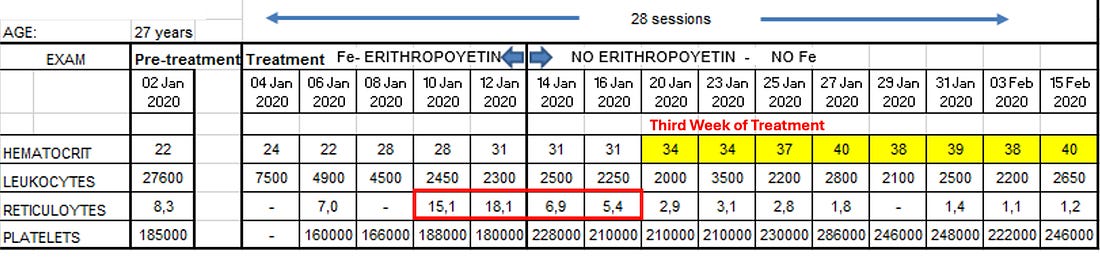

project involved treating approximately 85 patients, with the cure rate